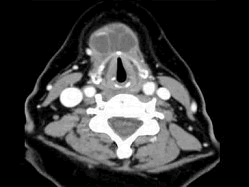

女,57岁,颈部不适,CT如图所示,应诊断为()

[单选题]女,57岁,颈部不适,CT如图所示,最可能的诊断是()A.咽囊囊肿B.鳃裂囊肿C.甲状舌管囊肿D.颈部淋巴管瘤E.颈部神经鞘瘤

[单选题]女,57岁,颈部不适,CT如图所示,最可能的诊断是( )。A.咽囊囊肿B.鳃裂囊肿C.甲状舌管囊肿D.颈部淋巴管瘤E.颈部神经鞘瘤